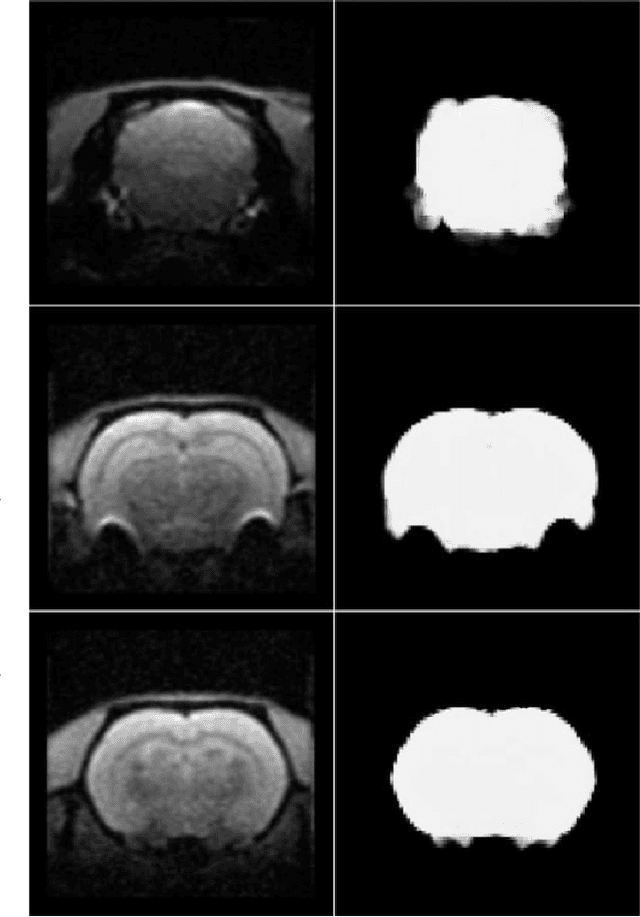

Abstract:Removing skull artifacts from functional magnetic images (fMRI) is a well understood and frequently encountered problem. Because the fMRI field has grown mostly due to human studies, many new tools were developed to handle human data. Nonetheless, these tools are not equally useful to handle the data derived from animal studies, especially from rodents. This represents a major problem to the field because rodent studies generate larger datasets from larger populations, which implies that preprocessing these images manually to remove the skull becomes a bottleneck in the data analysis pipeline. In this study, we address this problem by implementing a neural network based method that uses a U-Net architecture to segment the brain area into a mask and removing the skull and other tissues from the image. We demonstrate several strategies to speed up the process of generating the training dataset using watershedding and several strategies for data augmentation that allowed to train faster the U-Net to perform the segmentation. Finally, we deployed the trained network freely available.